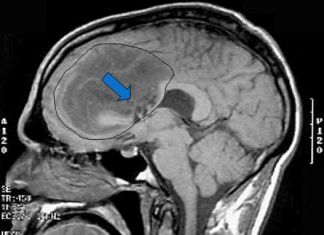

AMG 595, droga para el glioma maligno en ensayo experimental con...

La Universidad de California Cancer Institute es uno de los tres centros reconocidos a escala internacional para poner a prueba la seguridad de un...